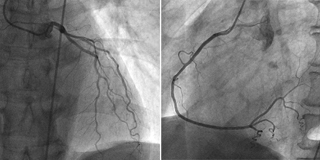

血管造影検査

血管造影検査は、動脈または静脈にカテーテルを挿入し、先端を目的部位(脳、心臓、肝臓等)まで進め、血管内に造影剤を注入し血管像や腫瘍像の撮影をする検査です。この検査により、血管の狭窄や閉塞、奇形、出血性病変、腫瘍性病変等を診断・治療することができます。

当院では、4台の血管撮影装置が稼働し、検査や血管内治療を行っています。心臓専用カテーテル室は2室となっており、増え続ける循環器疾患患者様に対しても365日24時間対応しています。

冠動脈